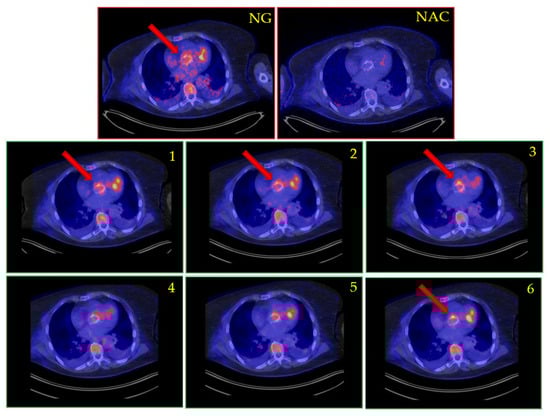

| PET results | Non-gated: IE confirmed Gated: Not available CardioFreezeTM: IE confirmed (fl+) | Non-gated: No IE Gated: No IE CardioFreezeTM: No IE | Non-gated: IE confirmed Gated: IE confirmed (fl+) CardioFreezeTM: Not available | Non-gated: Equivocal Gated: Equivocal CardioFreezeTM: Not available | Non-gated: No IE Gated: Not available CardioFreezeTM: IE confirmed | Non-gated: No IE Gated: Not available CardioFreezeTM: No IE | Non-gated: IE confirmed Gated: IE confirmed (fl+) CardioFreezeTM: IE confirmed (fl+) |